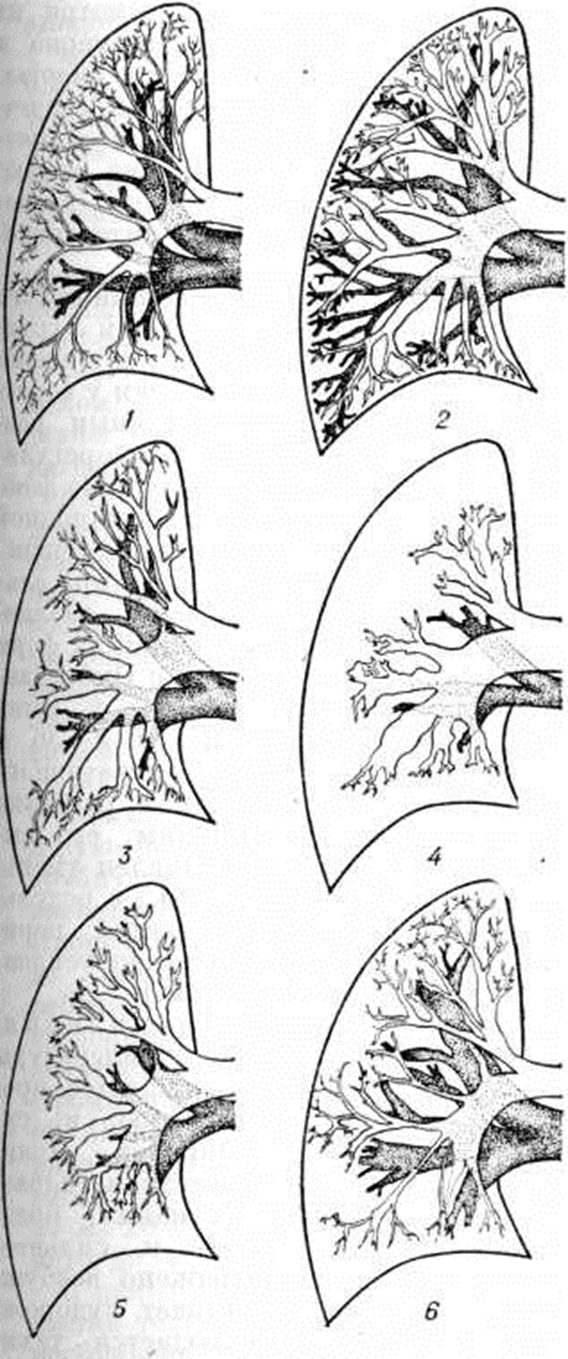

При рентгеноскопии и рентгенографии при выраженной прекапиллярной Гипертензия малого круга кровообращения определяется расширение лёгочного ствола, лёгочных артерий и их сегментарных ветвей (рисунок 6, а), а также выраженная гипертрофия правого желудочка сердца и особенно пути оттока крови. В периферических отделах лёгочных полей сосудистый рисунок обеднён, лёгочные вены сужены. При посткапиллярной Гипертензия малого круга кровообращения отмечается расширение как артерий, так и вен лёгких.

С помощью томографии (рисунок 6, а) возможно дифференцированное изучение лёгочных артерий и вен. По соотношению артериальных и венозных сосудов лёгкого можно выделить три типа изменений: 1) вены расширены, артерии имеют нормальный или незначительно увеличенный калибр — картина, характерная для лёгочной гипертензии при левожелудочковой недостаточности, панцирном сердце и митральном пороке (посткапиллярная Гипертензия малого круга кровообращения); 2) артерии и вены расширены — наблюдается, как правило, при врождённых пороках сердца (смешанная форма Гипертензия малого круга кровообращения); 3) крупные ветви лёгочной артерии расширены, а периферические ветви и лёгочные вены сужены — характерно для выраженной стадии первичной лёгочной гипертензии, комплекса Эйзенменгера, лёгочного сердца (прекапиллярная Гипертензия малого круга кровообращения).